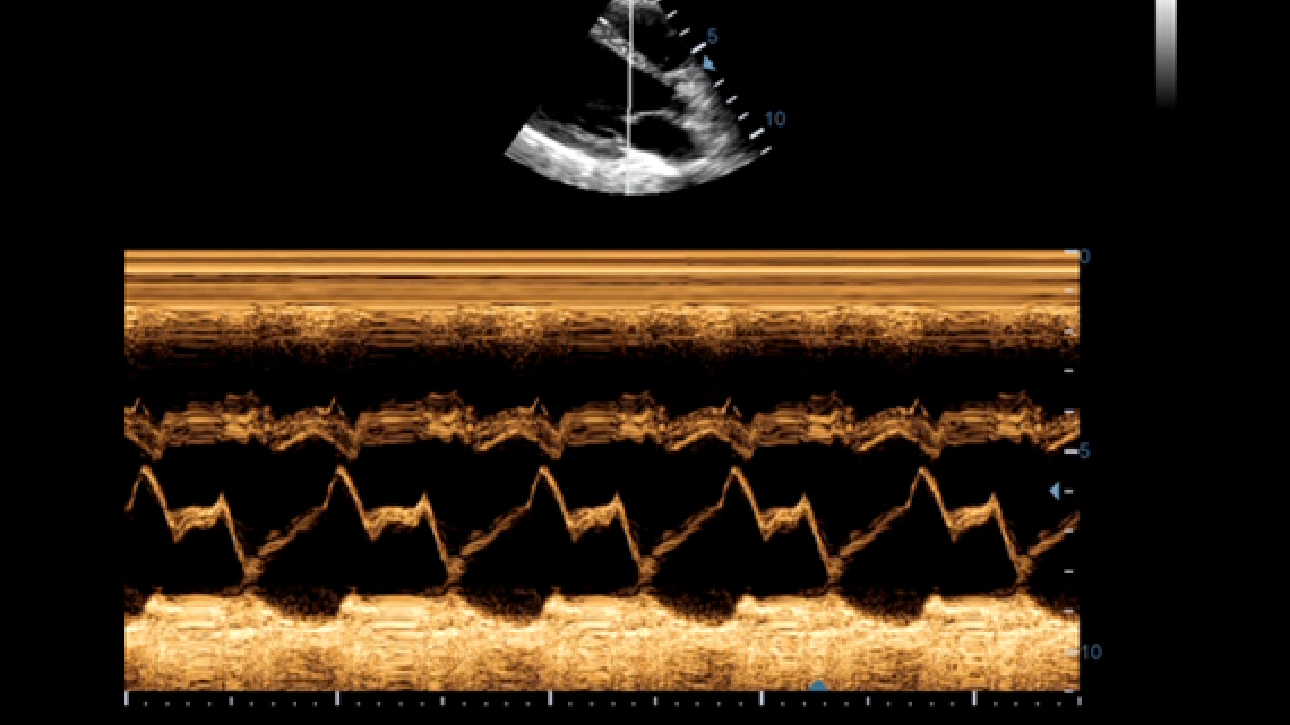

LVO (Left Ventricular Opacification)

Reveal structural and functional change of left ventricle with longer contrast agent duration and higher sensitivity with UWN+ technology.

Echo Boost

MindrayŌĆÖs unique adaptive signal processing technology with intelligent echo detection, designed to utilize the native signal-to-noise information to enhance the weak echo signals while suppressing the surrounding clutter noise, providing more balanced image brightness and improved visualization of myocardium tissue layers.